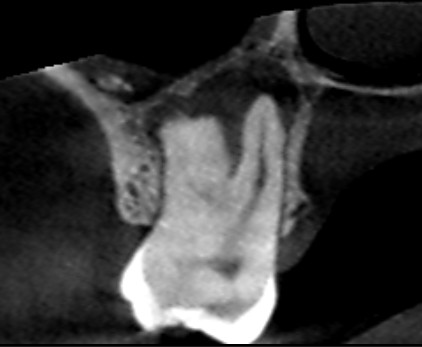

初診時の矢状断のCT画像です。

赤い矢印の先に黒い膿の影がみられ、膿は大きく埋伏している第三大臼歯(親知らず)に達しています。